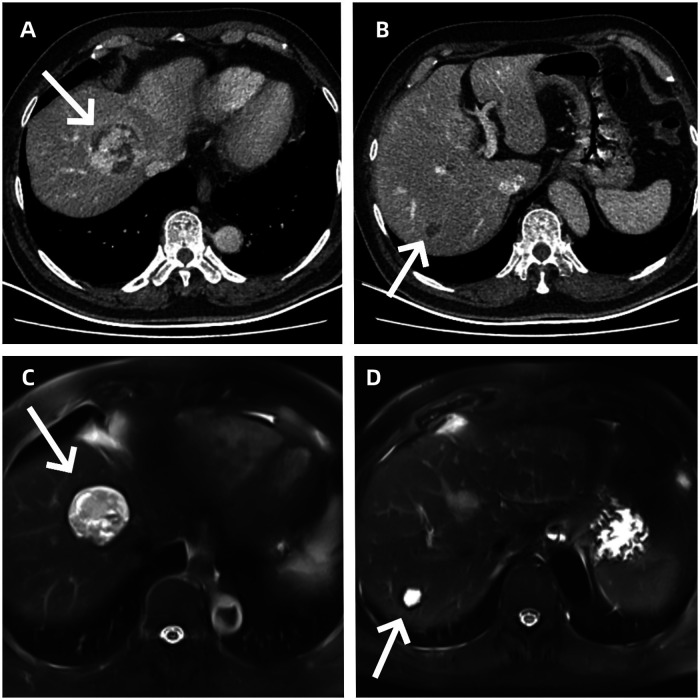

实验室和影像检查结果:入院后完善相关影像学和实验室检查。门静脉CT静脉造影(CTV)联合增强全腹CT显示肝脏S4段(45 mm)和S7段(15 mm)存在轻度低密度肿块,增强后呈现典型的转移性病变强化模式(图1A、B);全腹磁共振成像(MRI)进一步证实肝脏S4段(43 mm)和S7段(17 mm)存在软组织肿块,符合转移性病变的特征(图1C、D)。

图1. (A)增强CT显示肝脏左内侧叶肿瘤。(B)增强CT显示肝脏右后叶下段肿瘤。(C)MRI显示肝脏左内侧叶肿瘤。(D)MRI显示肝脏右后叶下段肿瘤。